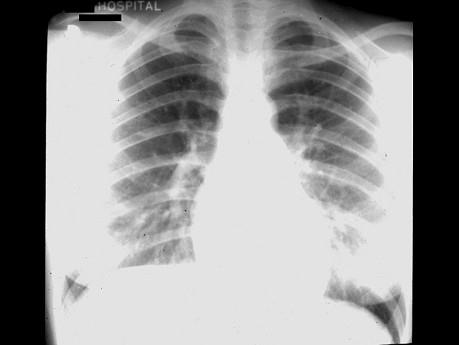

问题 男孩,3岁半,患先心病无发绀。X线检查如图所示:左心室增大,主动脉影增宽,肺野充血。考虑下列哪一种诊断可能性大 ( )

选项 A、法洛四联症 B、艾森曼格综合征 C、室间隔缺损 D、房间隔缺损 E、动脉导管未闭

答案 E